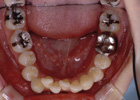

歯を抜いて治療した例 その1

治療前

治療途中

治療後